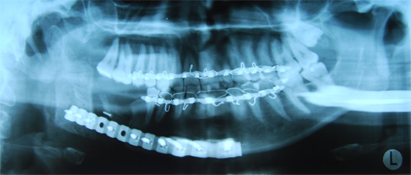

Un an et demi après la résection mandibulaire, la mandibule droite de la patiente a été reconstruite à l'aide d'une allogreffe osseuse déminéralisée et lyophilisée servant de support à l'os autogène prélevé de la crête iliaque postérieure (ill. 5). Le maxillaire inférieur allogénique a été évidé et rempli d'os autogène particulaire. Six mois après la reconstruction, la greffe osseuse montrait des signes cliniques et radiographiques de consolidation et la patiente demeurait exempte de signes et de symptômes d'ostéomyélite (ill. 6). L'occlusion finale était acceptable et la restauration sur implant des dents manquantes devrait être entreprise prochainement (ill. 7).

Ill. 6 : Radiographie panoramique du maxillaire inférieur reconstruit avec une grille mandibulaire prélevée d'un donneur décédé et un greffon spongieux particulaire autogène.